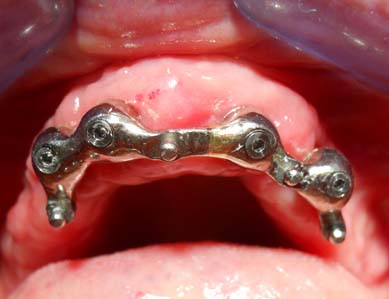

Paziente psichiatrico, con diabete di tipo II non insulino-dipendente, INR = 3. Il paziente lamenta instabilità della protesi totale inferiore. Si decide di intervenire inserendo 2 impianti che poi saranno uniti da barra per una successiva overdenture. Data la situazione ossea favorevole, il rischio di operare un paziente con tale anamnesi, e per minimizzare il trauma e con esso il sanguinamento peri- e post-operatorio, si decide di utilizzare la tecnica flapless.

( intervento eseguito da me in 20 min. )

2 MESI dopo il caso è stato finalizzato protesicamente.